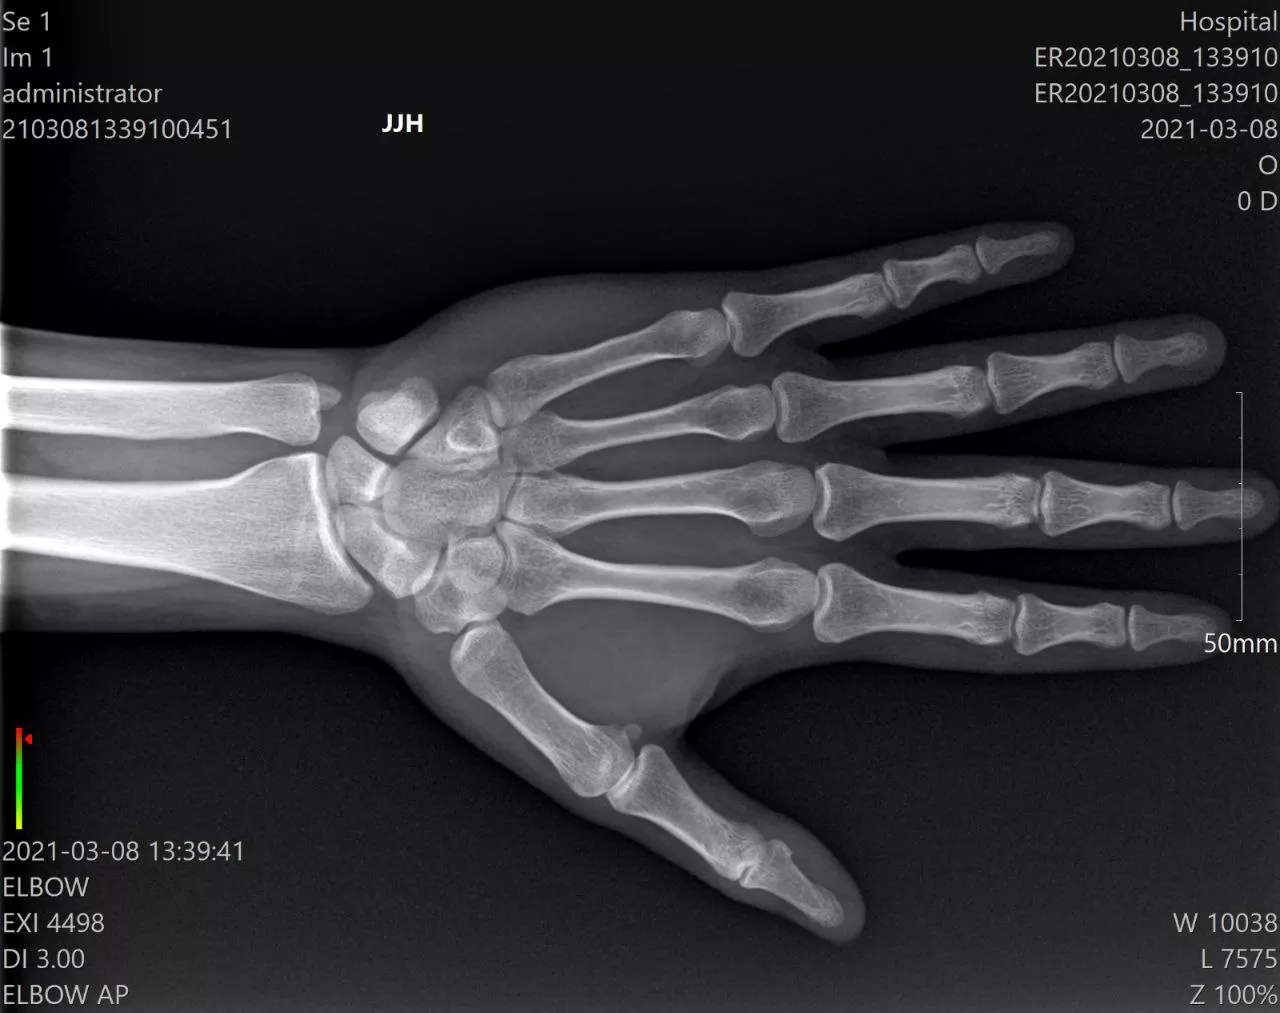

- Απεικόνιση υψηλής ανάλυσης: Παράγει εξαιρετική ποιότητα εικόνας με ανώτερη ανάλυση λεπτομέρειας

- Ταχεία επεξεργασία εικόνας: Δυνατότητες σχεδόν στιγμιαίας λήψης και επεξεργασίας εικόνας

- Ευέλικτη ισχύς: Λειτουργεί στα 40-80 kV / 3 mA, κατάλληλο για ορθοπεδική, αθλητιατρική, ποδιατρική και κτηνιατρική χρήση.

- Ορθοπεδική Χειρουργική: Διεγχειρητική απεικόνιση και μετεγχειρητικός έλεγχος

- Αθλητιατρική: Αξιολόγηση τραυματισμών στο γήπεδο και φροντίδα αθλητών